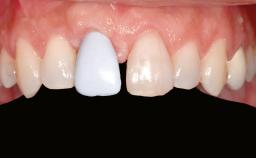

A 20-year-old woman was referred for implant therapy in 2004. Her medical history revealed no significant findings, and neither did she smoke nor take any medications. An extraoral examination revealed no abnormalities of the skin, hair or nails. The intraoral examination revealed only 11 permanent teeth clinically. These were normal in shape, size, and color. In addition, eight retained deciduous teeth (53, 62, 63, 71, 72, 73, 81, 82) were present. No abnormalities were detected during the general examination. The family history revealed that the patient’s father and two sisters were on record with similar conditions. The clinical examination revealed a thick gingival biotype. No recession of the attached gingiva was noted, but the retained deciduous teeth were mobile and unsightly. As a syndrome had not been diagnosed, the case was categorized as non-syndromic oligodontia.

Prosthesis Type FDP

Shape of Tooth Crowns Rectangular Triangular